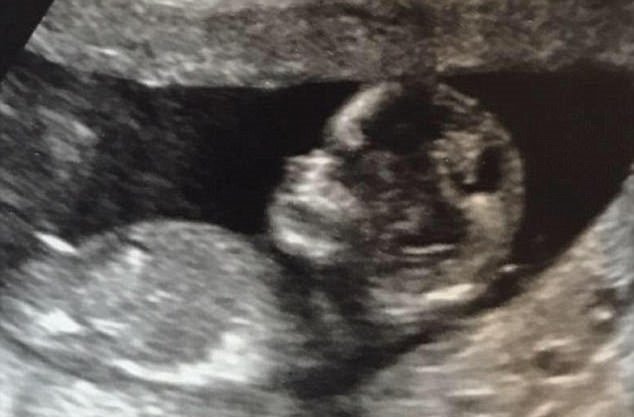

У главной героини этого материала, британки Сью Рэдфорд, 20 детей. Около года назад они с мужем узнали, что станут родителями в 20-й раз. Тогда они сделали фотографию, на которой был изображен снимок УЗИ с подписью: «10 мальчиков и 9 девочек. Этот ребенок станет 20-м».